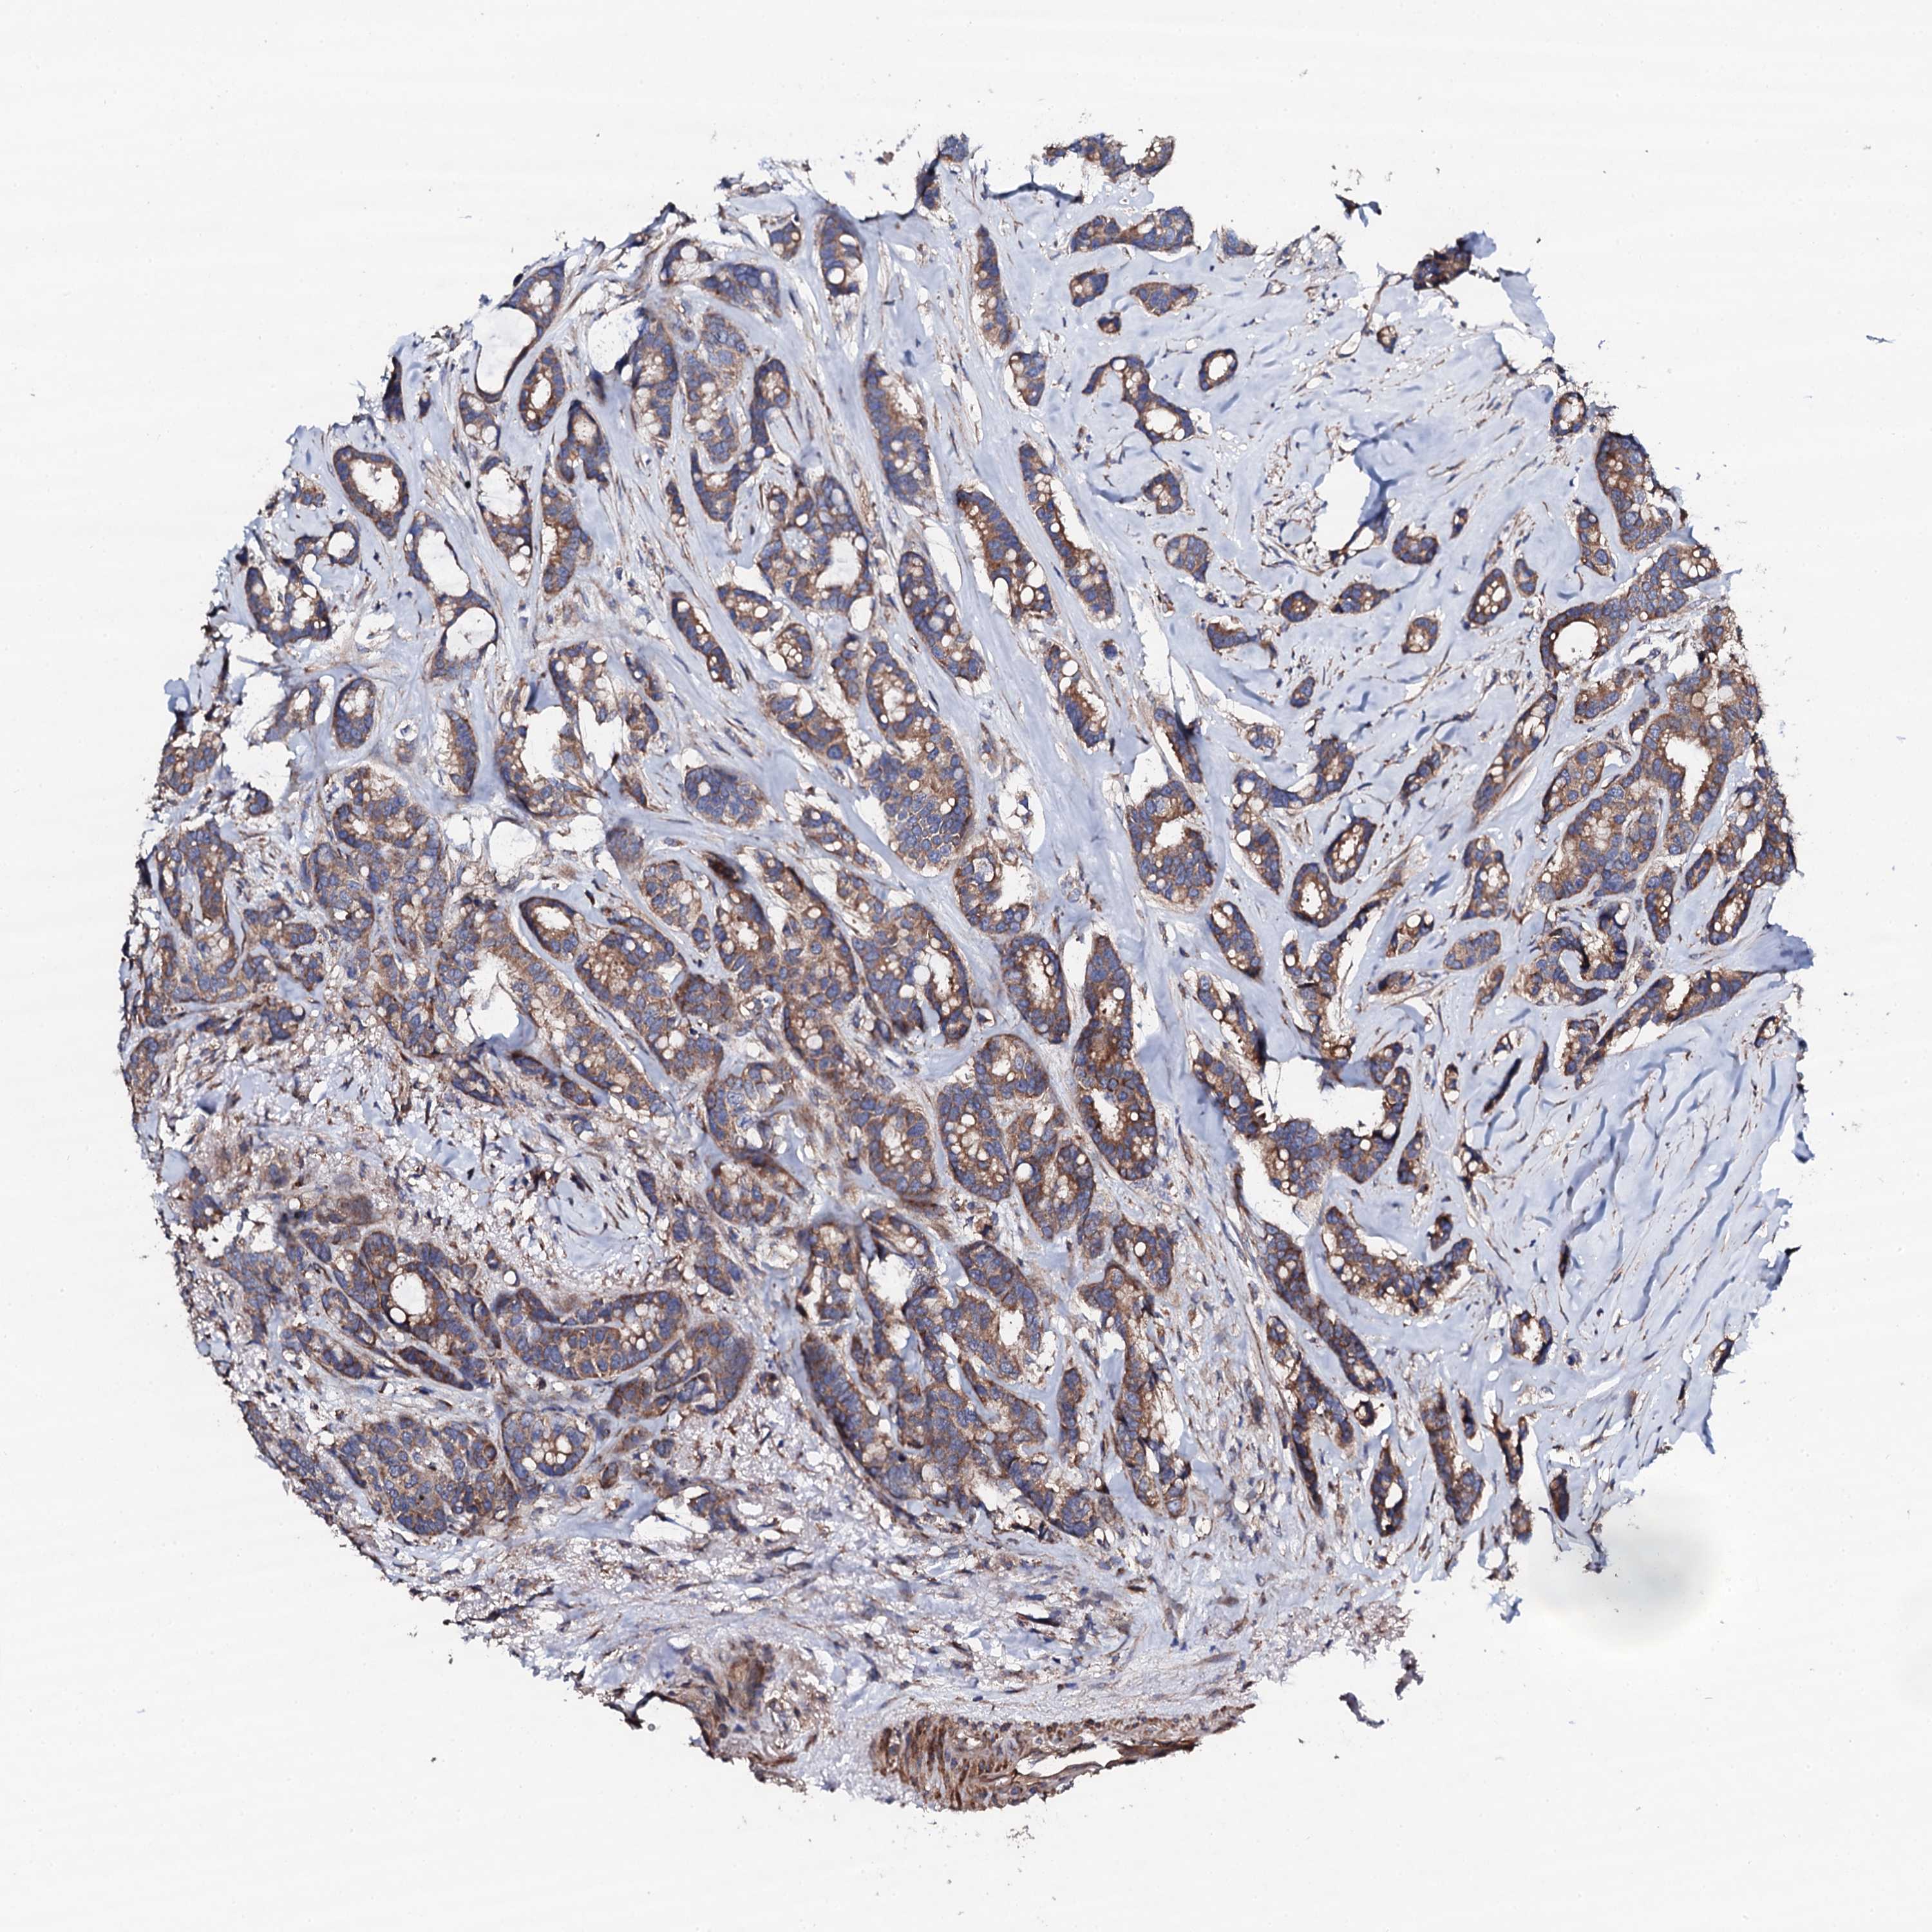

CANCER BREAST CANCER Show tissue menu

BRCA TCGA BRCA VALIDATION PROTEIN EXPRESSION

ANTIBODIES

AND

VALIDATION